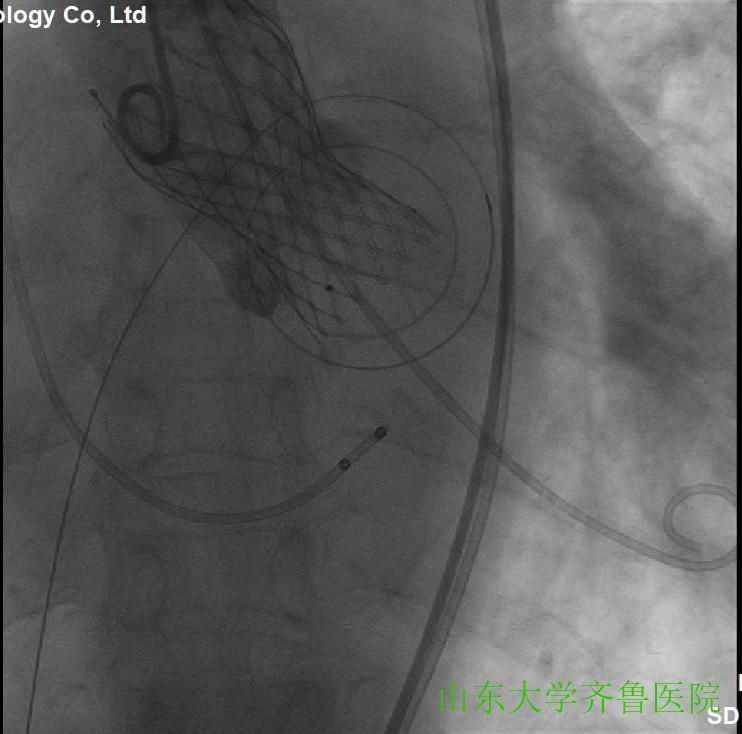

在手术室护士长翟永华及其护理团队、麻醉科吴剑波主任医师和杨绍忠主治医师的大力支持下,由心血管外科谷兴华主任医师、急诊心内科李传保主任医师、心内科安贵鹏副主任医师、心血管外科孙厚荣副主任医师及刘凯副主任医师、心脏超声室刘艳副主任医师和曹媛主治医师、放射科邵汉宏技师等在医院复合(Hybrid)手术室行一站式经导管主动脉瓣置换术(TAVR)+经皮二尖瓣球囊扩张成形术(PBMV)。手术先常规经颈静脉于右心室放置临时起搏导线并放置经食道TEE探头,行主动脉根部造影,明确主动脉瓣环平面、主动脉瓣钙化及返流情况(图1),导丝跨瓣入左心室并更换猪尾导管,测主动脉瓣跨瓣压差为76mmHg。选用24mm的擎源二尖瓣扩张球囊扩张2次,二尖瓣口面积由0.78?扩大至1.43?,并且二尖瓣无返流(图2)。选用20mmNuMed球囊,临时起搏心率180次/分,扩张狭窄的主动脉瓣(图3),应用26mmVenusA主动脉瓣介入瓣膜,准确定位、释放,造影、多体位透视及术中TTE显示介入主动脉瓣膜形态满意、无瓣周分流(图4-6)。术后即刻主动脉瓣最大跨瓣压差将至2mmHg。手术顺利,手术用时1小时40分钟,术后患者安返心脏外科监护病房。

图4选用26mmVenusA主动脉瓣介入瓣膜,定位,缓慢释放

图5临时起搏心率140次/分,缓慢释放介入瓣膜

图6释放介入瓣膜,形态、位置满意,造影时无瓣周分流